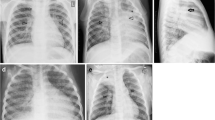

In children with inadequate immunity, the primary disease can progress contiguously or hematogenously [5, 34]. Contiguous progression of disease is seen as homogeneous parenchymal consolidation and lymphadenopathy. Compression of an airway by adjacent enlarged nodes results in overinflation (if partial obstruction) or atelectasis (if complete obstruction) because of smaller and more pliable airways in children [5, 11, 13, 14, 30, 35, 36]. The most reliable radiographic feature of lymphadenopathy is airway compression [13, 37] (Fig. 1). This lymphobronchial involvement/airway compression is strongly associated with confirmed pulmonary TB, significantly more frequently observed in infants compared to older children, although limited again by poor interobserver agreement [11, 12, 31, 33, 38]. Further imaging with cross-sectional modalities is thus recommended.

A 12-year-old boy with severe pulmonary tuberculosis with lymphobronchial involvement. a, b Posteroanterior (a) and lateral (b) radiographs of the chest show lobulated soft tissue densities in the hilar and mediastinal regions (arrowheads) representing enlarged lymph nodes, with narrowing of the left main bronchus (thick arrow) and leftward displacement of the trachea (thin arrow). c, d Contrast enhanced computed tomgraphy scan of the chest. The axial image on soft tissue window setting (c) demonstrates the typical central necrosis with a peripheral rim of enhancement in the subcarinal lymph nodes (arrowheads). The coronal image on lung window setting (d) better delineates the smooth narrowing of the left main bronchus (arrow) caused by the enlarged nodes

CT is the gold standard for the detection of lymphadenopathy and its complications [10, 14, 19, 30, 31, 33, 63, 64] such as airway compression by lymphadenopathy, termed “lymphobronchial TB” (Fig. 1). Presence, pattern (smooth or irregular) and degree of tracheal and bronchial compression causing segmental or lobar collapse or overinflation, bronchiectasis and obstructive pneumonia can be determined by CT [4, 5, 13, 19, 36, 38].

Children with lymphobronchial TB may initially manifest with unremitting cough, stridor and wheezing which may reflect partial airway obstruction. CT can assess this group of patients not only by detecting lymphadenopathy, but also by evaluating and staging associated airway compression and downstream lung parenchymal disease, thereby aiding clinicians to decide the course of treatment [13, 38, 63].

The staging of post-obstructive lung disease differentiates reversible disease from irreversible lung destruction and requires the administration of intravenous contrast. This staging and progression of disease depends on the degree of airway obstruction, whether partial or complete and presence of nodal erosion into the airway lumen. Reversible lung injury is treated conservatively, and includes air trapping, consolidation showing air bronchogram with or without atelectasis and consolidation with fluid bronchogram (“drowned lung”) with or without expansile pneumonia. Non-enhancement and cavitation are features of an irreversible and non-salvageable lung which is managed with lobectomy [13, 63].